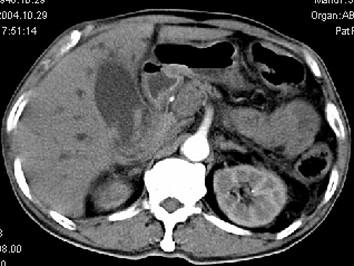

问题 男,58岁,患者右季肋区疼痛,皮肤黄染,可触及肿大胆囊,B超提示胆囊颈部肿块影,CT所见如图,最可能的诊断是 ( )

选项 A、慢性胆囊炎 B、胆囊腺肌增生症 C、胆囊癌 D、胆囊黄色肉芽肿 E、胆囊息肉

答案 C